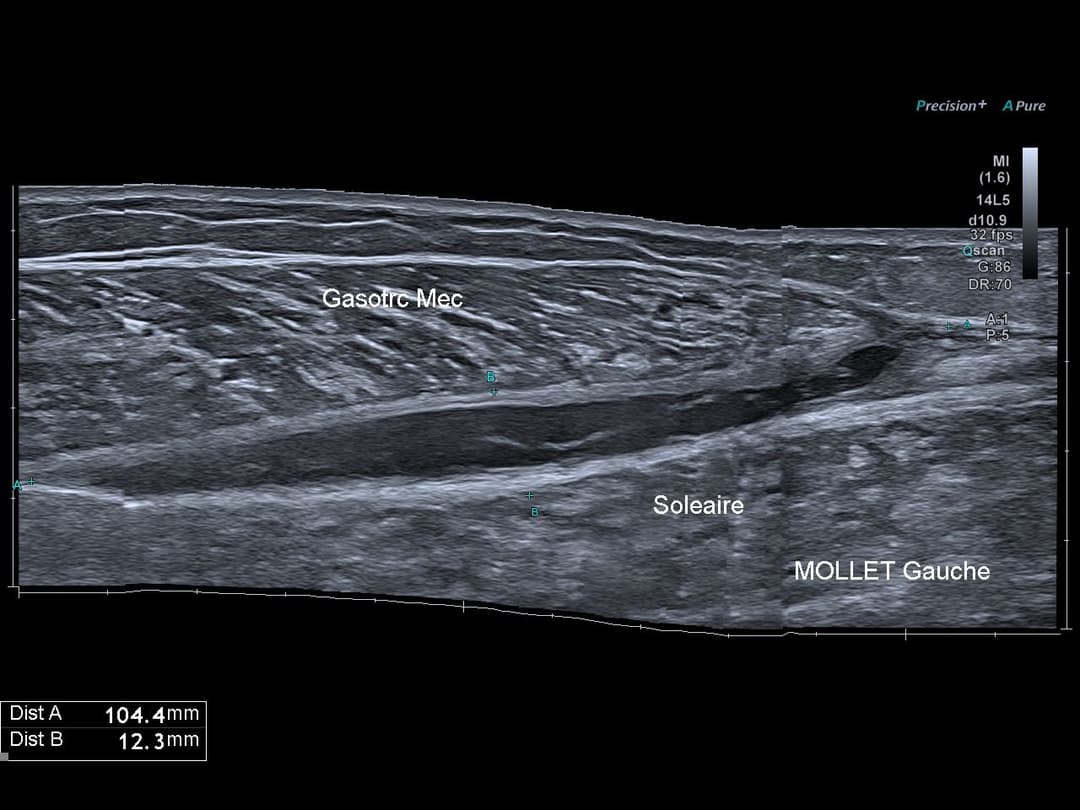

A 1 mois, hématome interaponévrotique ayant nécessité d'une ponction échoguidée

A 3 mois, développement d'un fibre cicatriciel, patient asymptomatique.